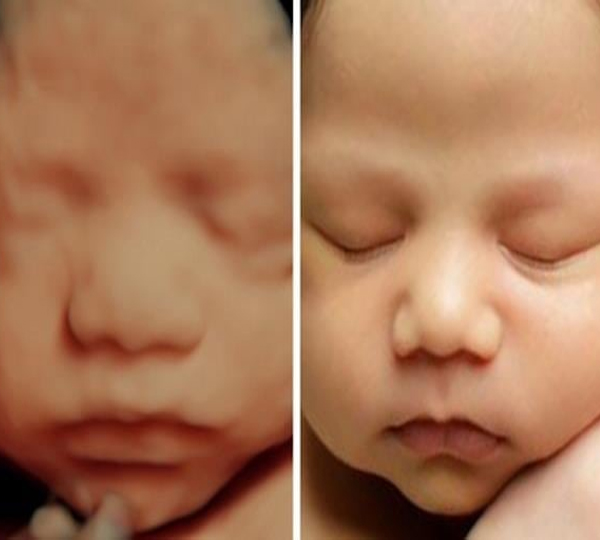

Genera imágenes con volumen, ademas de que se puede generar movimiento en las imagenes.

Se puede ver el bebé en movimiento y con total claridad. Su forma, volumen, textura de piel.